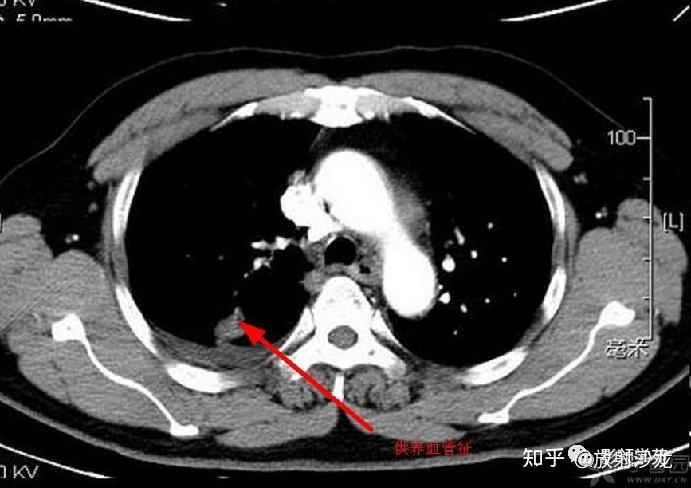

肺部wegener肉芽肿影像征象分析

图片尺寸903x586